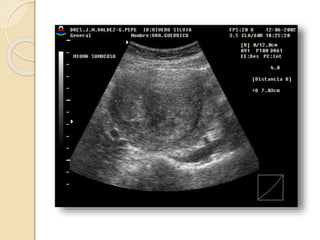

POLIPO ENDOMETRIAL

Se forman por una proliferación

anómala focal o multifocal de la capa

basal del endometrio y del estroma.

Son mas sensibles al estímulo

estrogénico y por esto es frecuente que

coexistan con una hiperplasia

endometrial.

Pueden ser sésiles o pediculados, únicos o múltiples y de

tamaño variable.

Suelen ser hiperecogénicos y en su espesor pueden

apreciarse pequeñas imágenes econegativas quísticas de

diferente tamaño.

Con la ayuda del Doppler color podemos identificar el

pedículo vascular.

La histerosonografía diagnóstica con nitidez la existencia

de pólipos endometriales. Incluidos los de dimensiones

reducidas, su numero, localización, su inserción y las

características del endometrio adyacente.